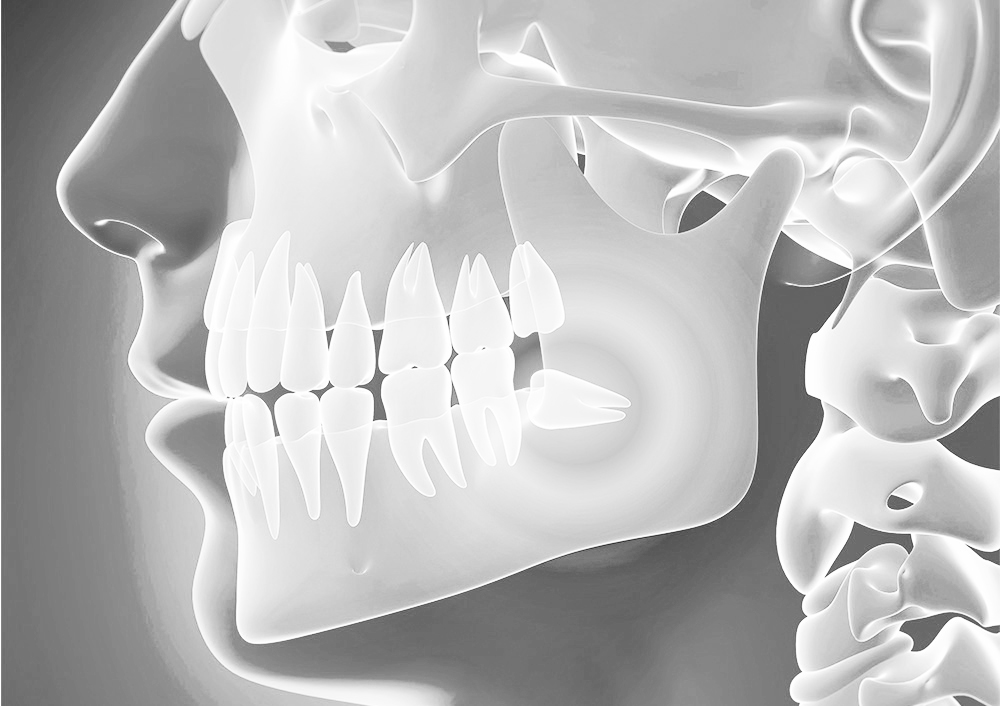

Q. 사랑니 뽑는 과정은 매우 힘든 건가요?

매복사랑니는 매복된 위치에 따라 난이도가 다릅니다. 보통 잇몸 수술을 동반해서 치아 분할, 골 삭제가 이뤄지므로 많이 불편할 수 있는 과정입니다. 최소절개, 최소삭제를 원칙으로 발치를 진행하여 수술 기간과 후유증을 최소화합니다.